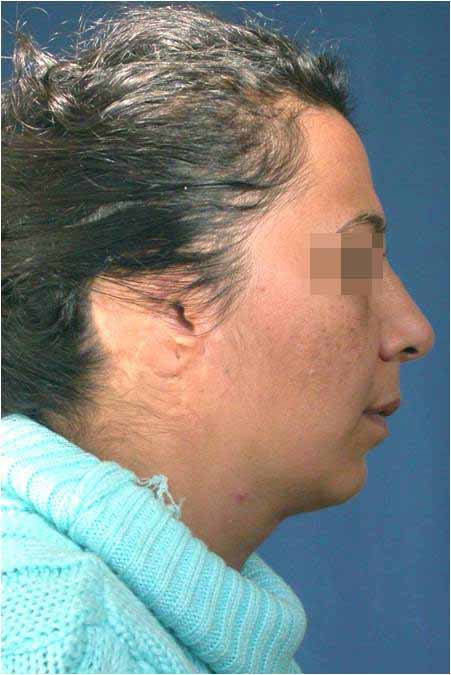

Лицева корекция преди и след лечението – случай на доц. Джоров